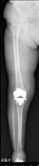

人工膝関節置換術、高位脛骨骨切り術

人工膝関節置換術後